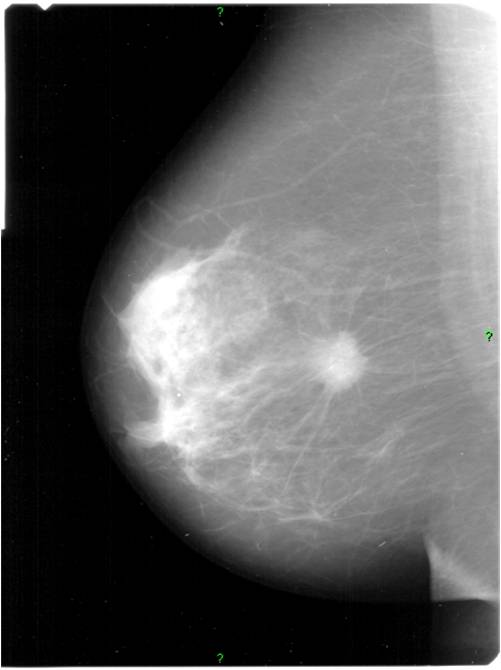

Image

Picture 3.